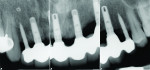

Eleven years later, the patient, who lived in London, returned to the New York University periodontology and implant dentistry department for follow-up. Radiographic evaluation demonstrated complete implant integration with no bone resorption around either the standard-diameter implants or the NDIs (Figure 16). One of the titanium tacks that secured the membrane had remained above the No. 7 NDI. Because the tack was well tolerated with no hard- or soft-tissue pathology, it was allowed to remain in place. Clinically, no signs of soft-tissue inflammation were noted (Figure 17 and Figure 18), and the patient reported complete satisfaction with the function and esthetics of his fixed restoration.